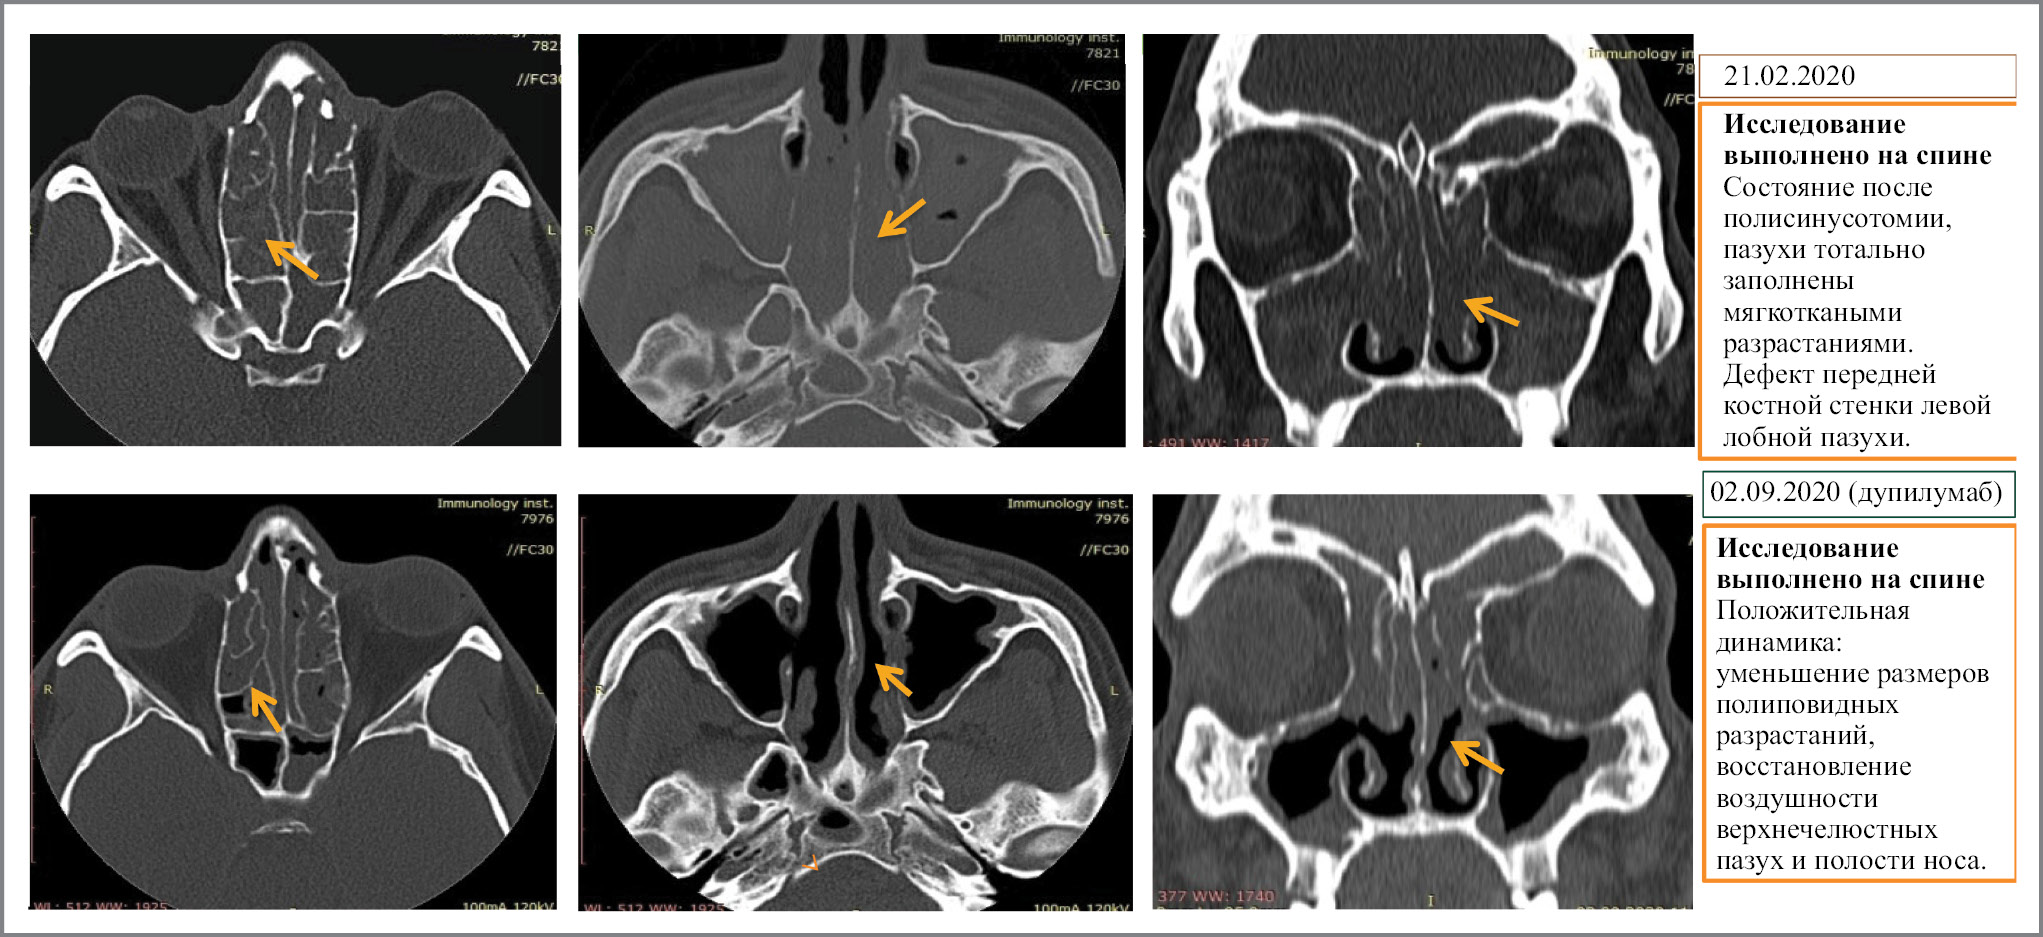

Клинический пример. Пациент Ж., 30 лет. Обратился с жалобами на одышку при физической нагрузке, приступы затрудненного дыхания, кашель с трудноотделяемой светлой мокротой, заложенность носа, боли и «чувство распирания» в области левого глаза, отсутствие обоняния. Страдает БА и ПРС в течение последних 12 лет. На момент обращения в качестве базисной ингаляционной терапии получал будесонид/формотерол (960/27 мкг/сут), монтелукаст (10 мг/сут) и СГКС (дипроспан 1,0 мл внутримышечно 4 раза в год), при этом не было контроля ни по одному из состояний: перечисленные жалобы сохранялись. Потребность в короткодействующих бронходилятаторах – до 3 раз в сутки. ИГКС в высоких дозах – постоянно. За текущий год отмечено 3 обострения по БА, по поводу чего пациент был дважды госпитализирован, количество курсов СГКС – 8 за год, перенес 7 хирургических вмешательств на околоносовых пазухах. На картине компьютерной томографии (КТ) у пациента практически нет воздушного пространства в околоносовых пазухах, процесс распространен и в полости носа, и в решетчатых лабиринтах верхнечелюстных пазух. В процессе хирургических вмешательств у пациента была разрушена бумажная пластинка решетчатого лабиринта, что привело к прорастанию полипов в область левой глазницы, вызывающему ощущение распирания в левом глазу, колоссальный отек, односторонний экзофтальм и косоглазие. Пациент практически не жаловался на присутствие БА, так как главную роль, определяющую качество его жизни, играл ПРС.

При оценке проявлений ХПРС: практически не беспокоит заложенность носа, после 4 мес лечения появилось обоняние, сократилась потребность в топических ГКС эндоназально. После осмотра оториноларинголога не было отмечено полипозных вегетаций (полипотомия не проводилась). SNOT-22 перешла в пределы нормальных значений (от 98 до 18 баллов). Четкая динамика видна на КТ за прошедший период: очистились верхнечелюстные пазухи, что привело к восстановлению носового дыхания (рис. 4). Благодаря применению дупилумаба у пациента радикально изменилось качество жизни.

Рис. 4. Результаты лечения. Мультиспиральная КТ околоносовых пазух в динамике.

Fig. 4. Treatment results. Multispiral computer tomography scan of the paranasal sinuses in dynamics.